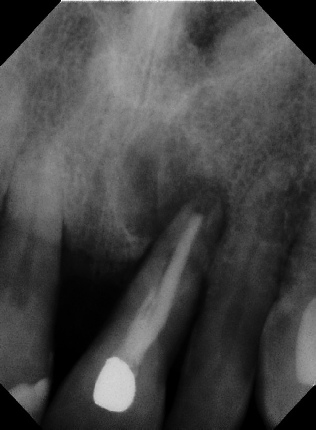

Cvek Pulpotomy 12 mos. Post-op Apexogenesis